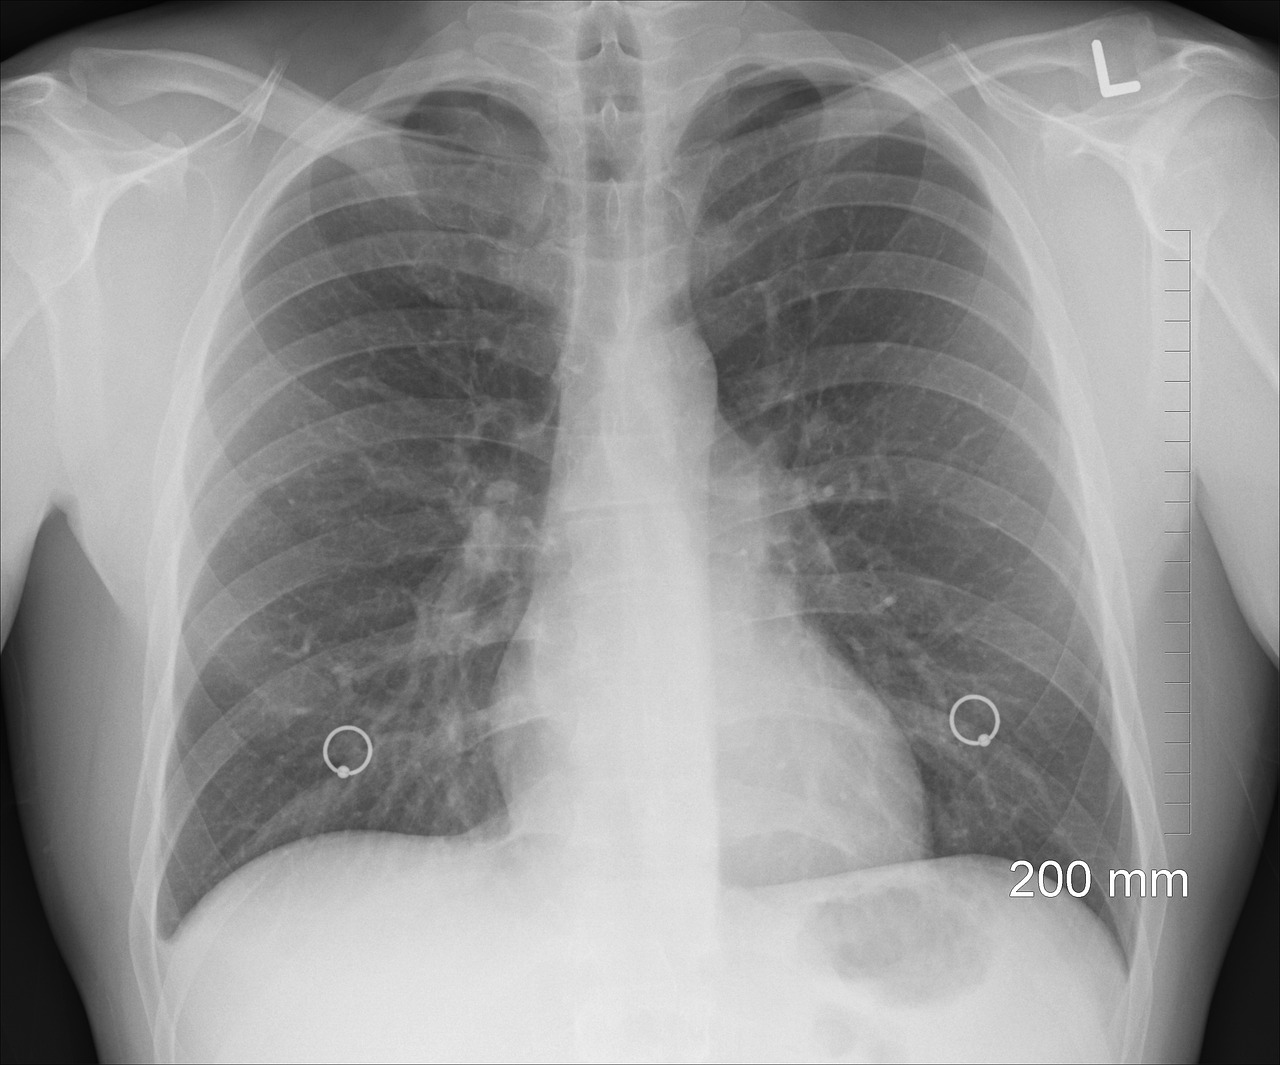

급성 폐렴은 말 그대로 ‘급작스럽게’ 발생하며, 비교적 짧은 시간 안에 증상이 악화됩니다. 일반적으로 48시간 이내에 고열, 심한 기침, 가래, 흉통, 호흡곤란 등의 증상이 동반되며, 특히 고령자나 만성질환자의 경우 급속한 호흡기 기능 저하로 이어질 수 있습니다. 급성 폐렴은 흔히 세균성 감염(폐렴구균, 헤모필루스 인플루엔자, 황색포도상구균 등)에 의해 발생하며, 즉각적인 항생제 치료가 필요합니다. 급성 폐렴은 환자의 면역 상태와 병원체에 따라 경증에서 중증까지 다양하게 나타납니다. 흉부 X선이나 CT에서 폐에 뚜렷한 염증 음영이 보이며, 대부분의 환자는 증상이 명확해 빠르게 진단이 가능합니다. 치료하지 않으면 패혈증이나 급성호흡곤란증후군(ARDS)으로 이어질 수 있기 때문에, 진단 즉시 항생제 투여와 산소 치료 등의 적극적인 대응이 필요합니다. 반면, 만성 폐렴은 증상이 천천히 시작되고 장기간 지속되는 것이 특징입니다. 기침, 미열, 전신 쇠약감, 체중 감소 등 비특이적 증상이 나타나며, 3주 이상 지속될 경우 만성 폐렴을 의심해봐야 합니다. 진행속도가 느리기 때문에 환자 본인도 질환의 심각성을 인식하지 못하는 경우가 많으며, 진단이 지연되기 쉽습니다.